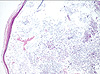

CASO N° 3 (Dr. Abel e Dr. Delgado)

Paciente do gênero masculino, 21 anos de idade, apresenta uma lesão no palato duro.